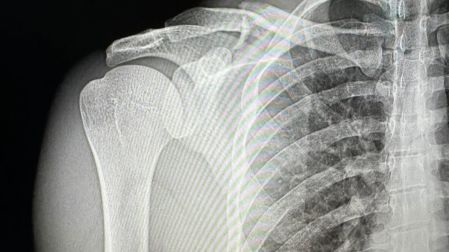

Natanael Cano sufrió un accidente mientras practicaba motocross, lo que le provocó una fractura de clavícula. El cantante de corridos tumbados compartió la noticia a través de sus redes sociales, donde publicó imágenes de su día realizando esta actividad y de los rayos X tomados en el hospital.

Las fracturas de clavícula suelen requerir inmovilización durante varias semanas y en algunos casos pueden necesitar intervención quirúrgica. Si bien el cantante no ha dado detalles sobre el tratamiento que seguirá, la recuperación de este tipo de lesiones puede tomar entre seis y ocho semanas.